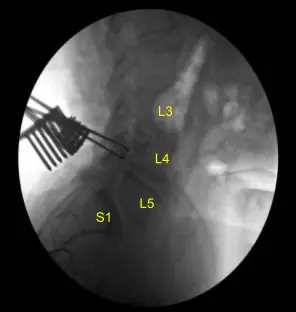

The patient was sterilely draped. CT scan was obtained. Data was transferred to the neuronavigation computer. Accuracy was verified. Neuronavigation techniques were used to morselized bone for arthrodesis autograft. Leksell rongeurs, Kerrison rongeurs and electric high-speed drill under continuous sterile irrigation were used to perform complete L4-5 laminectomy and facetectomies, completely neurolyzing with Penfield-Metzenbaum technique the L4, L5 and S1 nerve roots.

Epidural bleeding was controlled with Surgiflo hemostatic matrix and bipolar electrocautery. Bone bleeding was controlled with bone wax. L4-5 and L5-S1 interbody arthrodesis was performed by retracting the thecal sac with a nerve root retractor, performing annulotomy with a bayoneted #15 blade scalpel.

Post Op X-ray